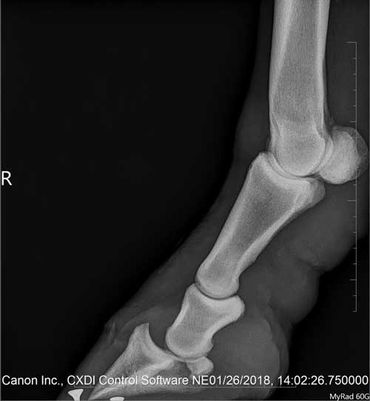

Back in August we to had her Coffin and Pastern joint injected because she was really lame.

Her bill for the injections was $ 640.